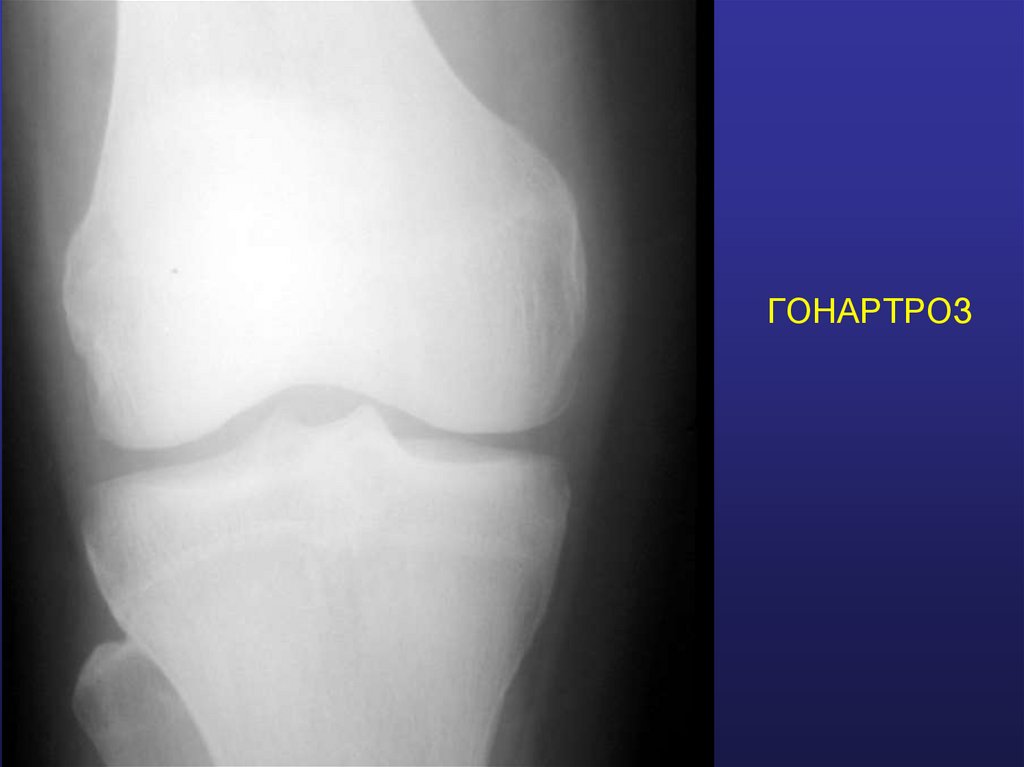

ГОНАРТРОЗ

28. ГОНАРТРОЗ